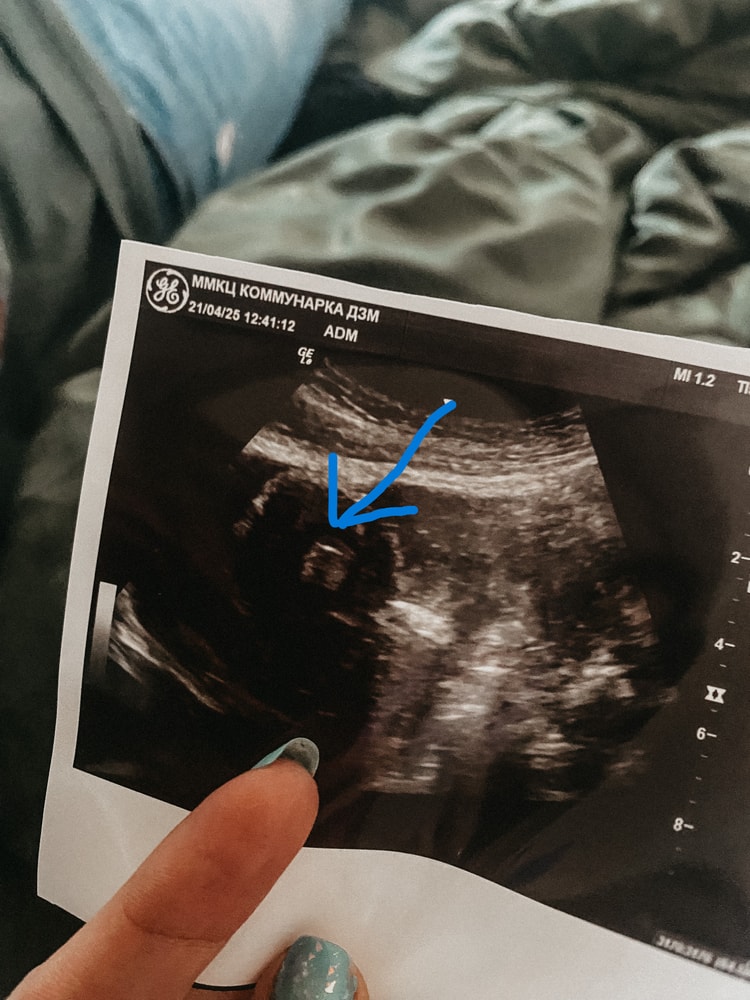

Танюша, здравствуйте! В кружочке, 23 недели)